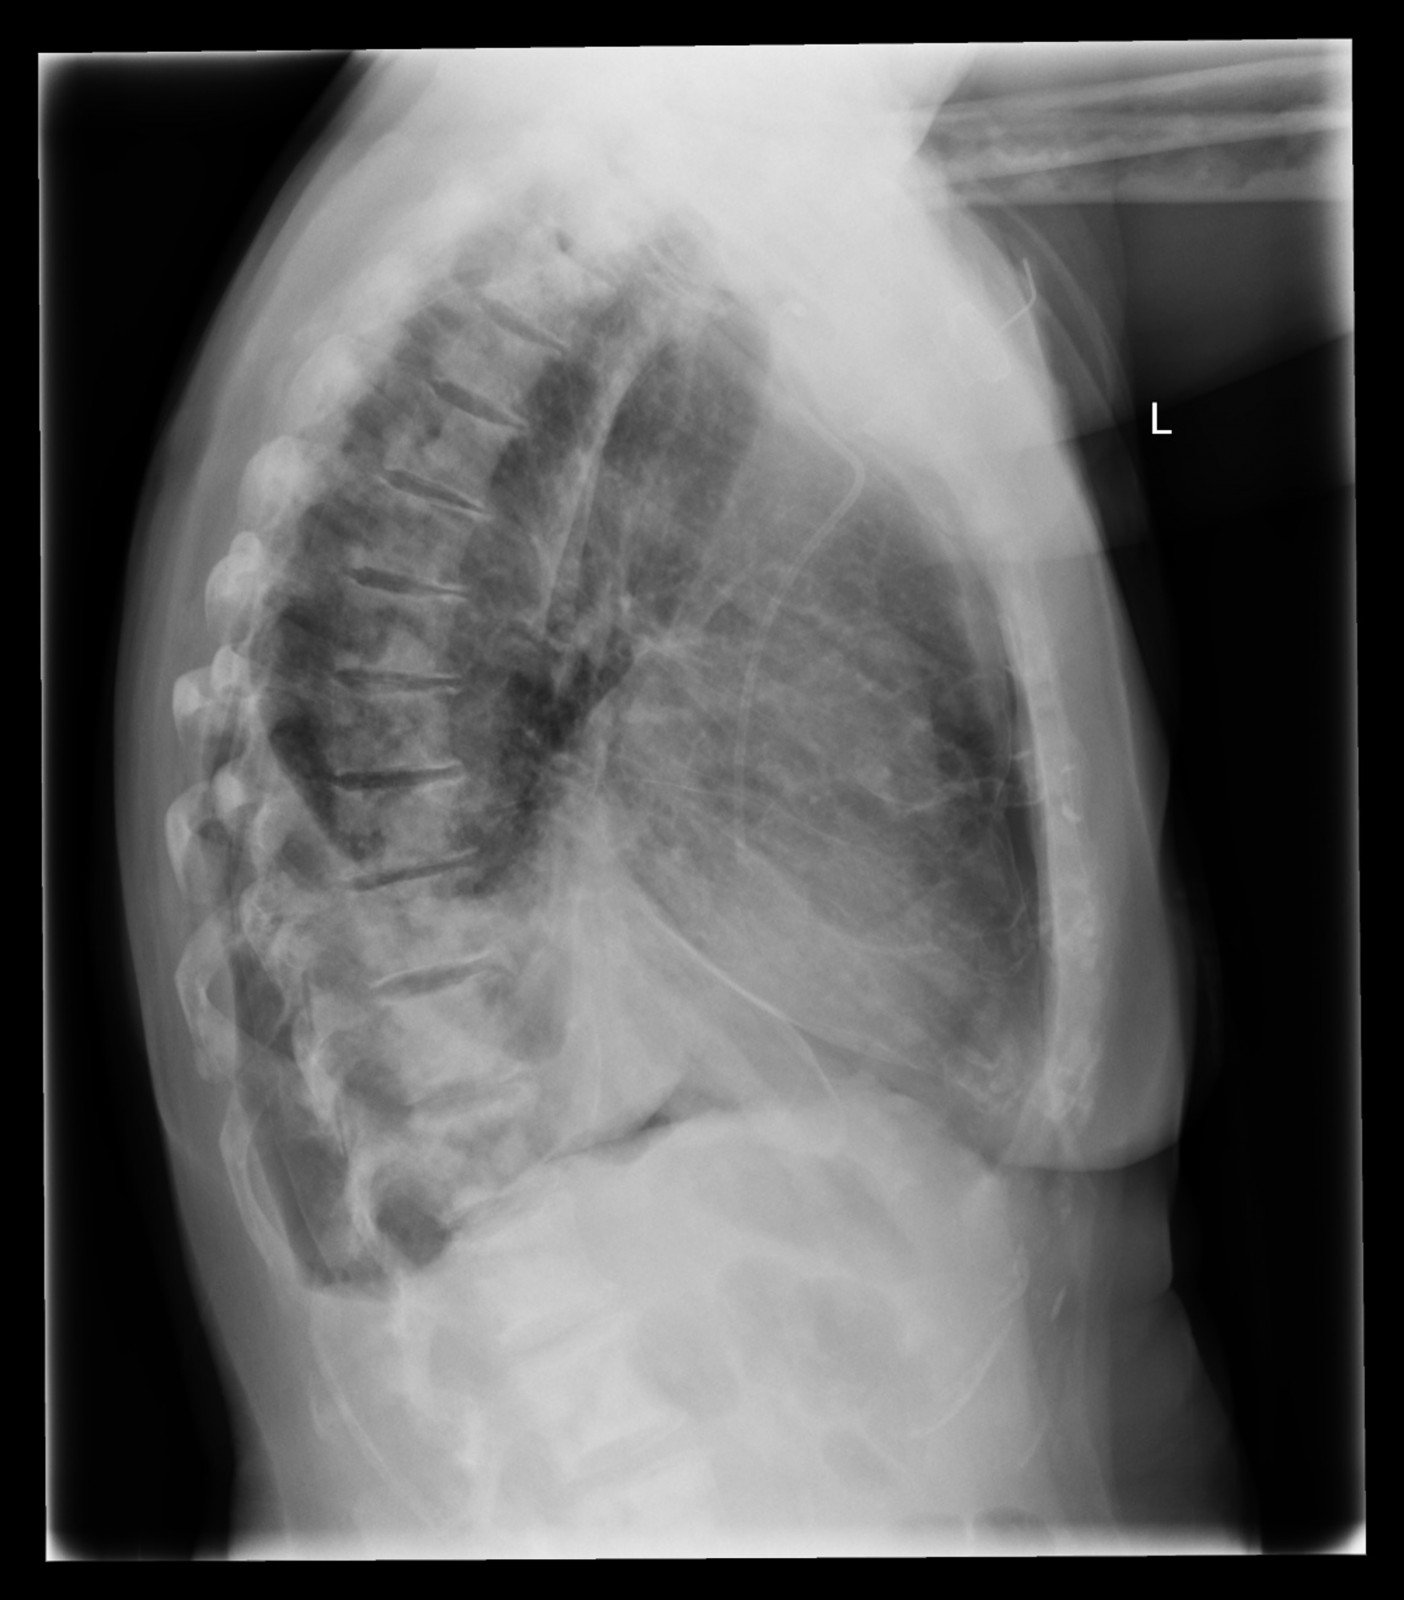

Röntgenfall des Monats Mai 2017 mit Auflösung

74 jährige Patientin mit diffusen Skelettschmerzen und akut aufgetretener Dyspnoe.

Z.n. Mammakarzinom rechts.